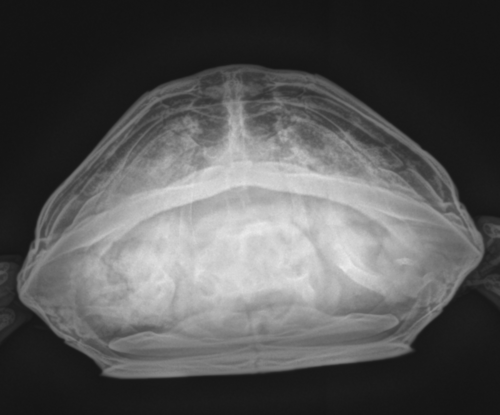

Для начала надо сделать цифровой рентген. В каких проекциях надо сделать, чтобы определить причины ? Или лучше все 3. С живота, профиль и сверху (черепашка головой вверх). И какие есть нюансы, чтобы врачу сообщить.

в идеале в 3х проекциях, настройки обычно  67кВ на 2мА/сек, также допустимо 50кВ на 6-8мА/сек

Похоже в моем случае все куда хуже и серьёзнее (((

Из того, что я вижу - у черепахи каловый завал или вообще непроходимость и уменьшен объем лёгких. Создать для Вас тему? Может помогут найти хорошего очного врача в Туле.